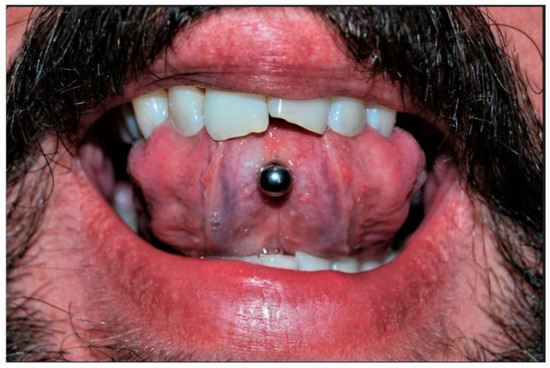

Figure 1.

Different locations for oral piercing include (A) the lingual frenulum, (B) the lower lip, (C) the body of the tongue, (D) the upper labial frenulum, and labret piercing [15].

Piercing is a body ornamentation that different civilizations have accepted since the past as a manifestation of self-expression [1]. Today, body piercing is widely noticed among people, especially young people [2,3]. People with body piercings stated aesthetics, personal preference, and fit with the subculture as the main reasons for piercings [4]. Information sources available to individuals generally fail to provide information about health risk factors or other health-related issues [5,6]. The incidence of body piercing has been reported to range from approximately 17 to 70% in different individuals [7,8]. Oral piercings may be placed in various combinations on the lips, tongue, cheeks, or uvula (Figure 1). Oral piercing is unsafe, has positional and systemic hazards, and is associated with various complications [9]. Abnormal tooth wear, grinding, cracking, and gingival recession are late complications [10]. In addition, infection, abscess, and endocarditis can be considered severe systemic complications of oral piercing, which may even be life-threatening [11].